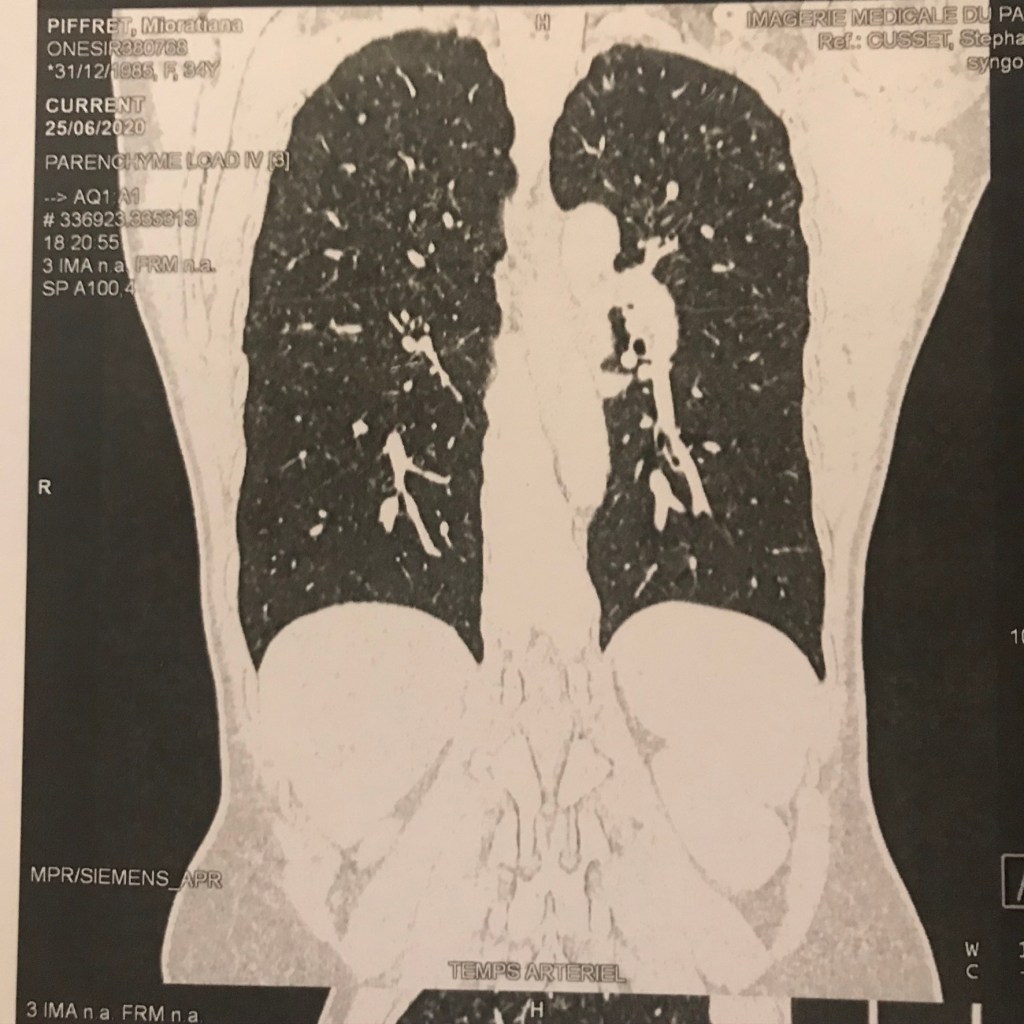

- La radiologue : « Vous êtes essoufflée, Madame? »

- Moi: « Pardon, non, je cours tout le temps, ça va bien ! Mais pourquoi ? »

- La radiologue : « La bonne nouvelle, ce que ce n’est pas un cancer. Par contre, votre scanner montre que vous avez une sarcoïdose pulmonaire: une maladie rare qui touche les jeunes dont la cause est inconnue avec l’accumulation de granulomes dans les organes»

- Mon médecin traitant le lendemain: « Mme P., il faut qu’on se voit ! Il faut faire des examens complémentaires, voir le pneumologue, l’ophtalmo, le cardiologue, faire une épreuve d’effort, peut-être prendre des corticoïdes…Vous avez des sueurs nocturnes ?».

- Moi, surprise : « Euh non. Mais oui, d’accord, à ce soir alors ! ».

Quand elle raccroche, je réalise que c’est la première fois en 10 ans qu’elle m’appelle. Je regarde enfin le compte-rendu de scanner : « Stade II » et les clichés. Oups, je n’ai pas de symptômes certes mais mon ganglion à l’aine droit et le scanner de mes poumons montrent bien que mon corps se défend !

Je cours quand même et je cherche à savoir si je ressens un truc qui cloche. Rien du tout, je suis en pleine forme et je savoure le fait d’être en vie.

[…] il faut aussi que je me soigne, pour l’instant j’ignore comment va évoluer ma sarcoïdose. J’ai l’impression que le fait d’être sportive contribuer à mon état […]

[…] répondu que non. Je préparais mon premier marathon et ça ne me gênait pas du tout. J’étais tombée des nues quand elle m’avait montrée mon scanner avec l’état de … Elle m’avait aussi dit: “La bonne nouvelle, c’est que ce n’est pas un […]